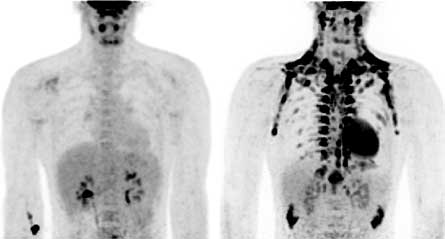

Brown fat shows up (black) in a PET-CT scan of a man after an hour-long exposure to chilly temperatures (right) but is not as apparent in a scan done at room temperature (left).